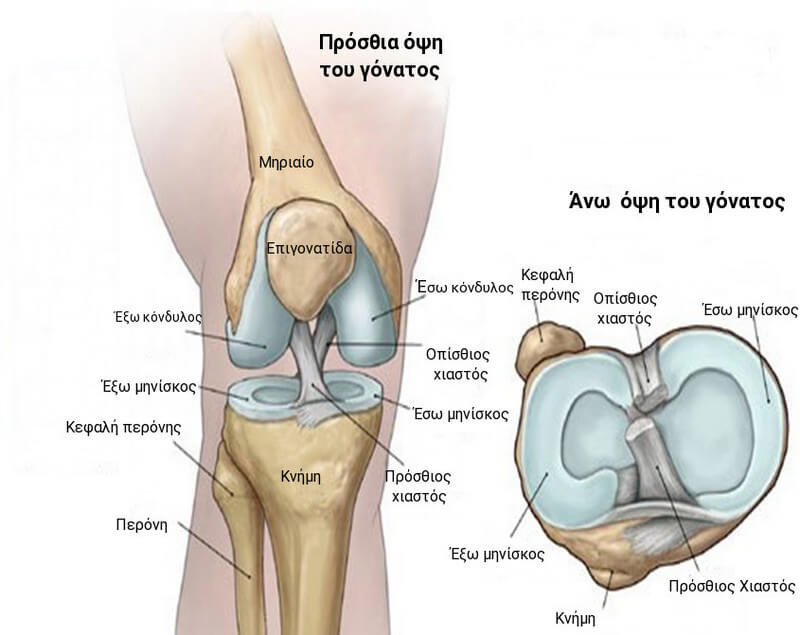

Εικόνα 1: Φυσιολογική ανατομία γόνατος

Το γόνατο αποτελείται από το κάτω άκρο του μηρού (μηριαίοι κόνδυλοι), το άνω άκρο της κνήμης (κνημιαία γλήνη) και την επιγονατίδα. Τα άκρα αυτών των τριών οστών καλύπτονται με αρθρικό χόνδρο, μια λεία ουσία που προστατεύει τα οστά και τους επιτρέπει να κινούνται ομαλά μέσα στην άρθρωση.

Οι μηνίσκοι βρίσκονται μεταξύ του μηρού και της κνήμης. Αυτές οι χόνδρινες σφήνες σχήματος C δρουν ως "αμορτισέρ" που απορροφούν κραδασμούς της άρθρωσης.

Μεγάλοι σύνδεσμοι συγκρατούν το μηρό και την κνήμη και παρέχουν σταθερότητα. Οι μεγάλοι μύες του μηρού και της κνήμης (τετρακέφαλος, οπίσθιοι μηριαίοι, γαστροκνήμιος) δίνουν δύναμη στο γόνατο και είναι υπεύθυνοι για την κίνησή του.

Όλες οι υπόλοιπες επιφάνειες του γόνατος καλύπτονται από μια λεπτή επένδυση που ονομάζεται αρθρικός υμένας. Αυτή η μεμβράνη απελευθερώνει το αρθρικό υγρό που λιπαίνει τον χόνδρο, εξαλείφοντας σχεδόν την τριβή σε ένα υγιές γόνατο.